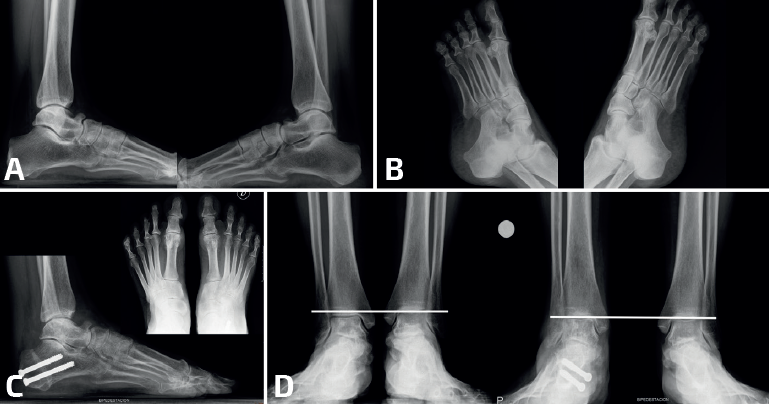

- Calcaneocuboidea: las coaliciones calcaneocuboideas suelen encontrarse en combinación con otras coaliciones (Frost y Pensieri) y también en el contexto de cuadros sindrómicos como el de Crouzon(26,27,28). Revisando nuestra casuística de coaliciones, los autores encontraron un caso de una paciente no sindrómica con una coalición aislada calcaneocuboidea bilateral que cursó con un pie plano valgo muy sintomático. La cirugía, consistente en una osteotomía varizante de calcáneo, mejoró la deformidad en valgo y la clínica hasta conseguir que la paciente estuviera asintomática (Figura 3).

- Múltiples/Masivas: las coaliciones tarsales múltiples/masivas (dos o más de dos en el mismo pie) pueden presentarse como casos aislados no sindrómicos o asociados a otros problemas dentro de un síndrome (Figura 4). Se han descrito casos no sindrómicos de coaliciones combinadas calcaneonavicular, talonavicular y talocalcánea, con frecuencia bilaterales(26,50), y también afectando a la articulación tarsometatarsal(51). La mayoría son asintomáticas y algunas cursan con inestabilidad y entorsis de repetición en el paciente adolescente(50). En algunos casos observamos que la clínica depende del desarrollo de reacciones de estrés en los huesos limítrofes, como en el caso de un paciente con coaliciones tarsales talocalcáneas y naviculocuboideas y con dolor en la cuña intermedia(52). Aunque la mayoría mejoran con tratamiento conservador, existen casos publicados con cirugía de resección con mejoría de los síntomas(50,53,54,55,56,57). En muchas coaliciones múltiples/masivas del tarso, el tobillo (tibiotalar) tiene que adaptarse para poder trabajar como una tibiotalar y una subtalar a la vez, lo que conlleva un crecimiento adaptado a la función, formándose un tobillo cóncavo-convexo (ball and socket en la literatura anglosajona)(58)(Figura 5). En la mayoría de los casos, el hallazgo es casual y el paciente está asintomático. En línea con otras coaliciones, en los pacientes sintomáticos la clínica deriva de un pie plano-valgo. Las soluciones mecánicas consisten en el uso de plantillas con un buen gradiente supinador o en una cirugía de realineación mediante una osteotomía supramaleolar de cierre con base medial(59,60). En algunos pacientes con artrosis subtalar o tibiotalar avanzadas, los procedimientos de realineación pueden combinarse con artrodesis(61,62).

- Corrección de la alineación, sin actuar sobre la coalición: en coaliciones óseas con deformidad (habitualmente en plano valgo). La osteotomía más habitual es la varizante de calcáneo, en coaliciones óseas talonaviculares, calcaneocuboideas y múltiples/masivas. Este tratamiento es el más frecuente en nuestra experiencia (Figura 6). Pero si existe un abducto del pie, una osteotomía de alargamiento de la columna lateral con una osteotomía de tipo Evans puede corregir la deformidad y mejorar el dolor. La supinación residual del antepié en coaliciones múltiples/masivas puede precisar de una plantarización del primer radio con una osteotomía de tipo Cotton. En pies con coaliciones tarsales masivas que originen tobillos cóncavo-convexo, las osteotomías supramealeolares permiten mejorar la valguización del retropié y la sintomatología dolorosa. El cambio de paradigma del tratamiento mediante cirugías de realineación sin actuar sobre la coalición ha derivado del tratamiento de las coaliciones talocalcáneas. De hecho, recientemente hemos formulado y publicado una nueva clasificación de coaliciones talocalcáneas con unas indicaciones de tratamiento que son extensibles a la mayoría de las coaliciones atípicas con una desaxación(64).